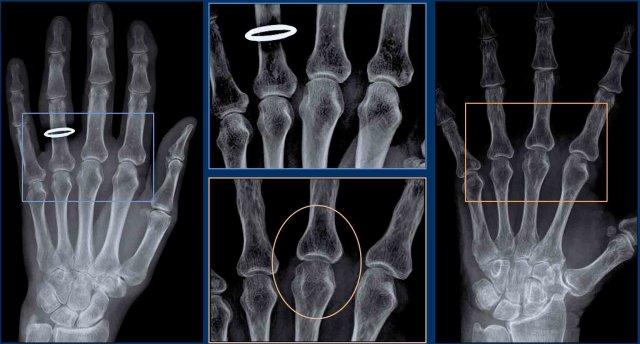

Xương – mật độ

Thay đổi mật độ xương biểu hiện dưới dạng loãng xương hoặc xơ cứng xương.

Loãng xương cạnh khớp (hình) thường gặp trong viêm khớp dạng thấp và không gặp trong viêm xương khớp. Mất khoáng xương cạnh khớp phát triển do tình trạng tăng sinh mạch máu của màng hoạt dịch và mô mềm bị viêm.

Xơ cứng xương dưới sụn thường gặp trong viêm xương khớp. Cũng gặp ở bệnh nhân viêm khớp thần kinh.

Hình ảnh

Đây là hai ví dụ về loãng xương cạnh khớp ở bệnh nhân viêm khớp dạng thấp.

Tình trạng loãng xương có thể rất kín đáo.

Có thể hữu ích khi điều chỉnh cài đặt độ rộng cửa sổ (hình chi tiết ở giữa) hoặc nhìn qua mi mắt khép hờ để nhận ra tình trạng loãng xương.